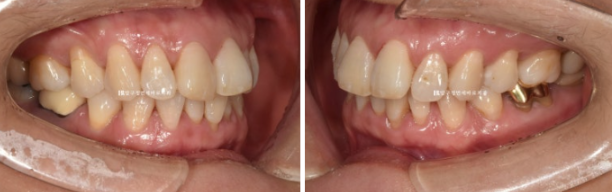

50대 환자분께서 앞니가 점점 뻗치고 틀어져서 교정을 위해 내원하셨습니다.

오래 전 발치교정을 이미 끝냈는데, 나이가 들면서 점점 앞니가 틀어져 앞니 부분교정을 위해 오셨습니다.

위 앞니 두개가 튀어나와있고 회전이 되어있습니다.

정식용어는 아니지만 이것을 나비치아 라고 부릅니다.

이 정도면 인비절라인 라이트로도 충분히 교정이 가능합니다.